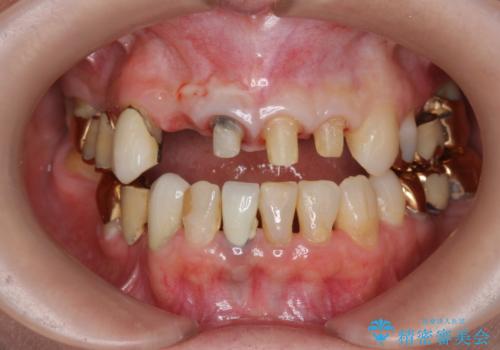

- 前歯の痛み・排膿・ぐらつきの改善を求めて来院されました。

視診・X線写真検査より根尖性歯周炎が認められ再治療が必要な状態です。

再根管治療を行うべくクラウン除去を行ったところ、右上側切歯に保存不可能な垂直性の破折が認められたため抜去が必要になりました。

即切歯の抜歯を行う場合犬歯を含めたブリッジによる補綴計画を立てることが多いですが、今回は犬歯から大臼歯にかかる大きなブリッジが既に装着されていたため予算とご希望を相談し前歯のみの延長ブリッジ補綴で治療を行っていくこととしました。